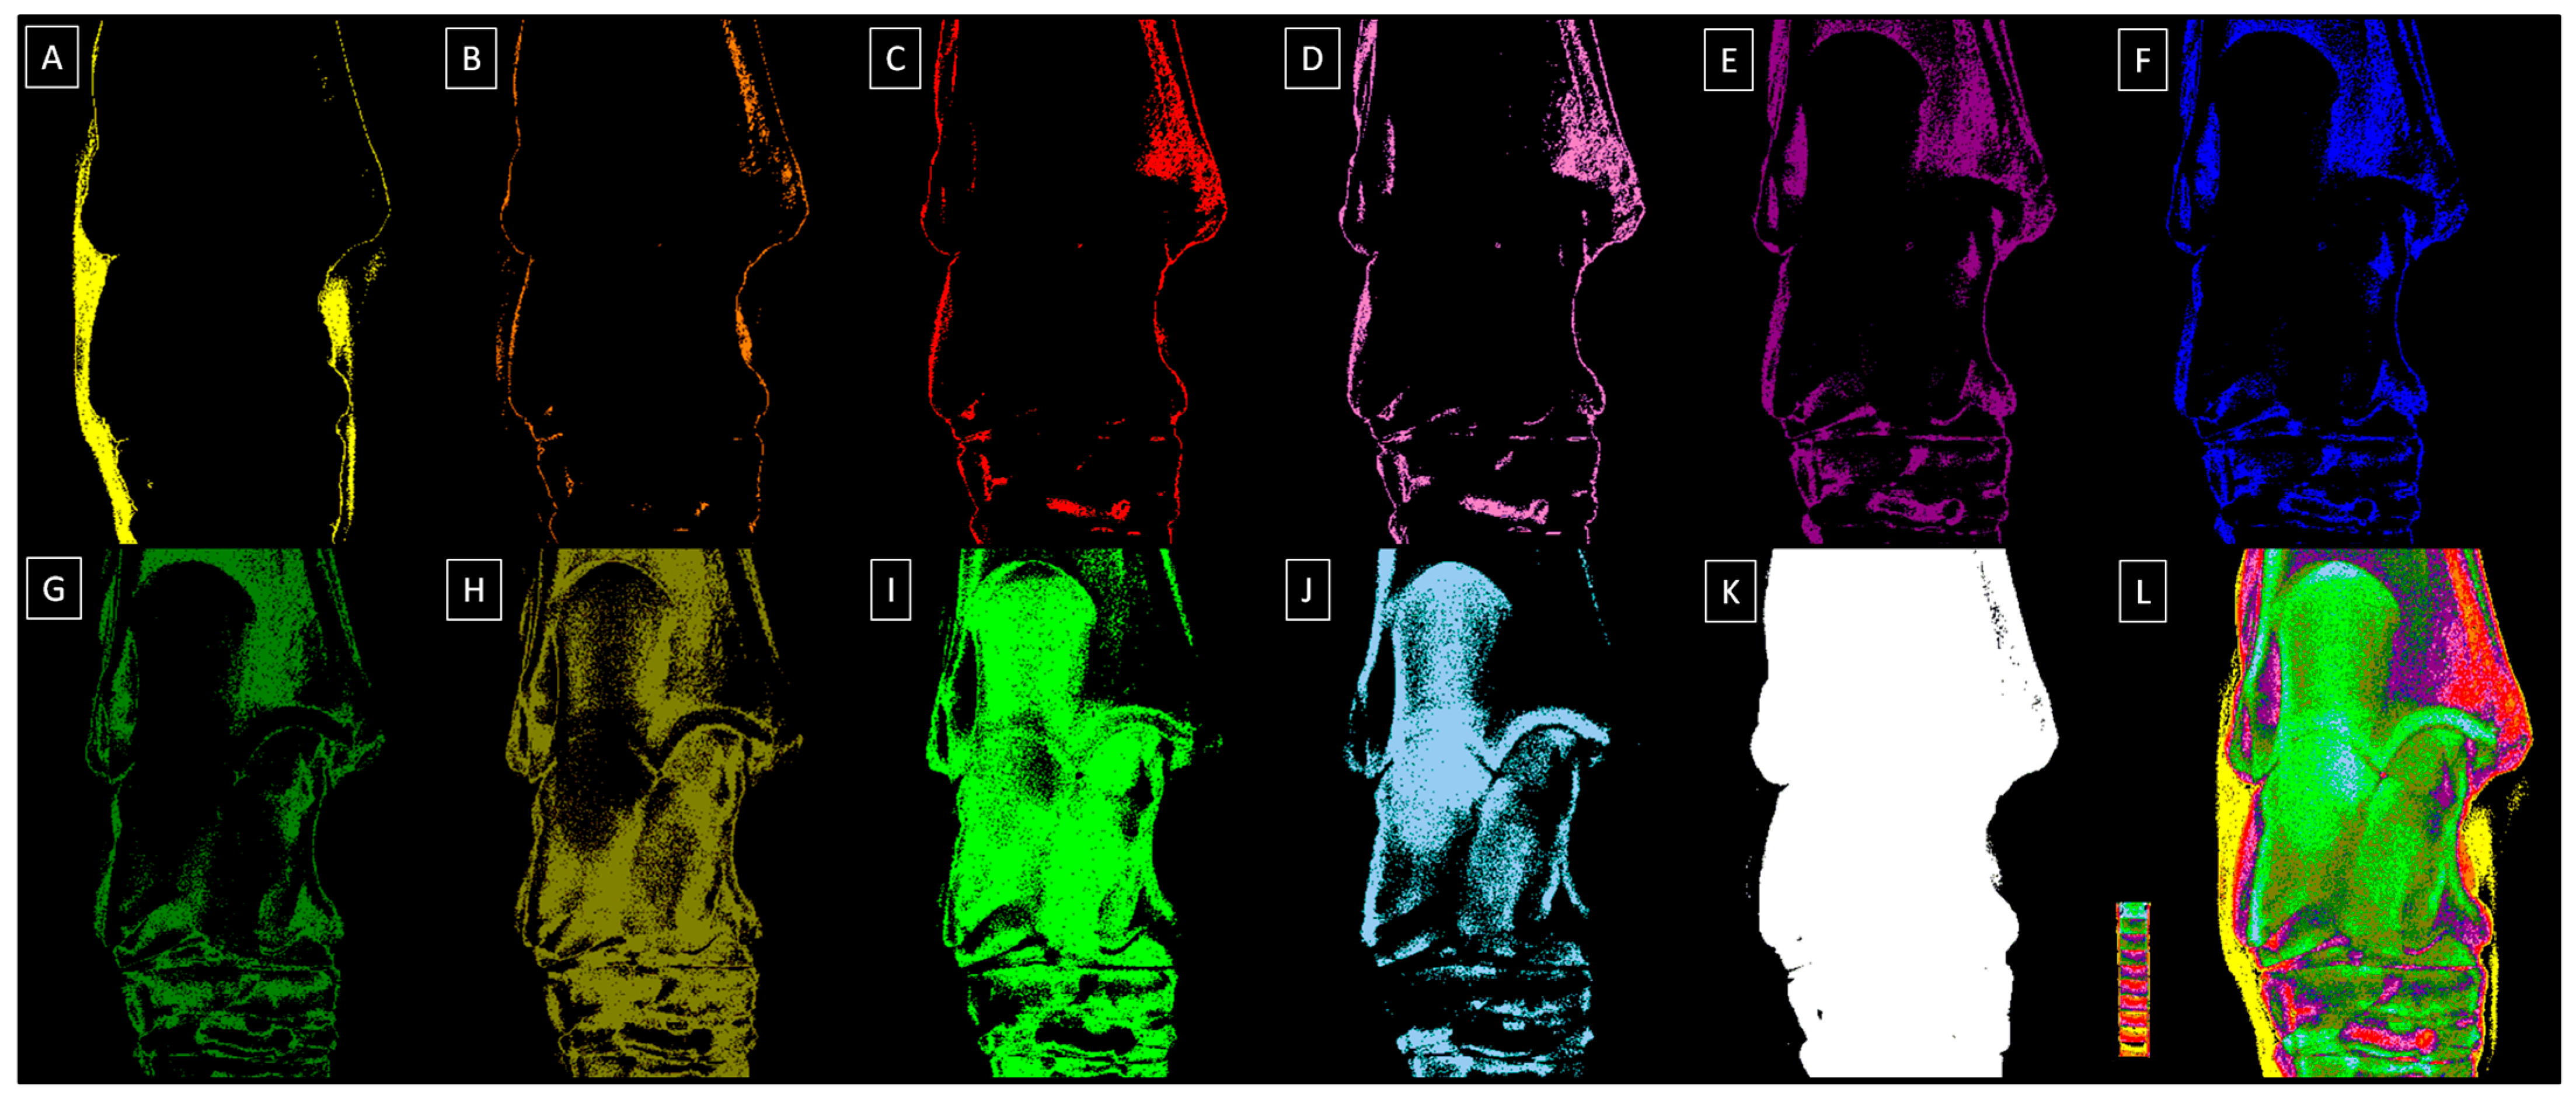

2.2. Radiograph Processing

2.3. Radiograph Quantification

| Decomposition | S1 | S2 | S3 | S4 | S5 | S6 | S7 | S8 | S9 | S10 |

|---|---|---|---|---|---|---|---|---|---|---|

| Relative density (HU) | 1009 ± 163 | 1212 ± 111 | 1407 ± 98 | 1600 ± 134 | 1804 ± 112 | 2011 ± 99 | 2204 ± 107 | 2400 ± 133 | 2607 ± 129 | 2803 ± 147 |

| Color | Yellow | Orange | Red | Light purple | Dark purple | Dark blue | Dark green | Navy green | Light green | Light blue |

| HEX code | #FFFF00 | #E08000 | #FF0000 | #E080C0 | #800080 | #0000FF | #008000 | #808000 | #00FF00 | #A6CAF0 |